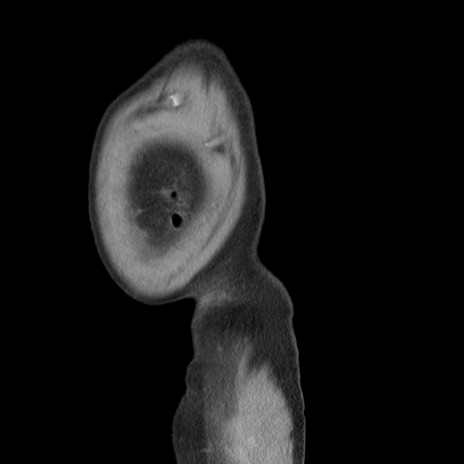

横断像

【症例】 60歳代男性

【主訴】 腹部膨満、嘔吐

【現病歴】5日前頃より倦怠感を認め食事量減少し4日前の朝嘔吐、食事摂取困難となった。 3日前近医受診し点滴施行され整腸剤などを処方された。 当日他院を受診し、腹部膨満著明、炎症反応の上昇(CRP10.8、WBC11200)あり、紹介受診となる。

【身体所見】 意識JCS1 受け答えがはっきりしないBP 111/57mHg、 P 67bpm、、BT35.2°C、SpO2 97%(RA)、 腹部:膨隆、打診で鼓音あり、全体的に圧痛有り、腸蠕動音(-)、反跳痛ははっきりせず。

【データ】WBC 11400、CRP 14.20